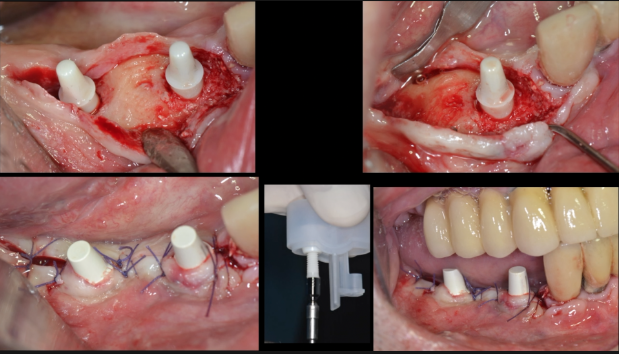

In this case presentation, the patient

suffered from a failed dentition in the maxilla and is planned to be restored with an

implant retained fixed hybrid denture. This video demonstrates the step-by-step

approach of the implant placement in the maxilla, including a titled implant

to avoid the sinus. Plaster impression was taken immediately after surgery and

an immediate temporary metal-acrylic denture was fixed to the implants.